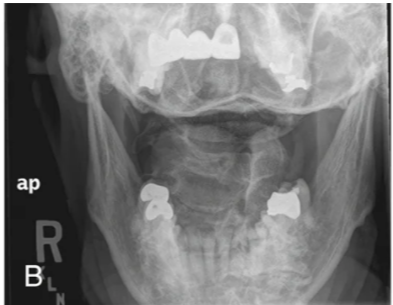

axiolateral oblique of the mandibular body

how is the head positioned to demonstrate the body of the mandible in the axiolateral oblique projection

30 degrees toward the IR

ramus

how must the head be positioned to best demonstrate the ramus of the mandible in an axiolateral projection

lateral